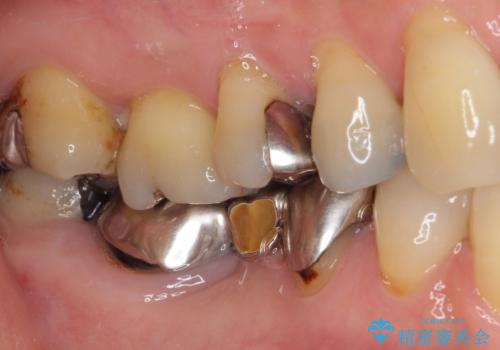

前歯のみならず、奥歯の銀歯や下顎前歯のデコボコなど、色々と気になる部分を治したいとのことでした。

前歯は抜歯が必要であったので、抜歯を行い、その後歯肉移植をおこなった上でオールセラミックブリッジによる補綴治療を行うこととしました。

下顎と上顎臼歯部については矯正治療を行い、奥歯の欠損部位はオールセラミックブリッジを、その他の銀歯はセラミックインレーなどにより治療を行うこととしました。